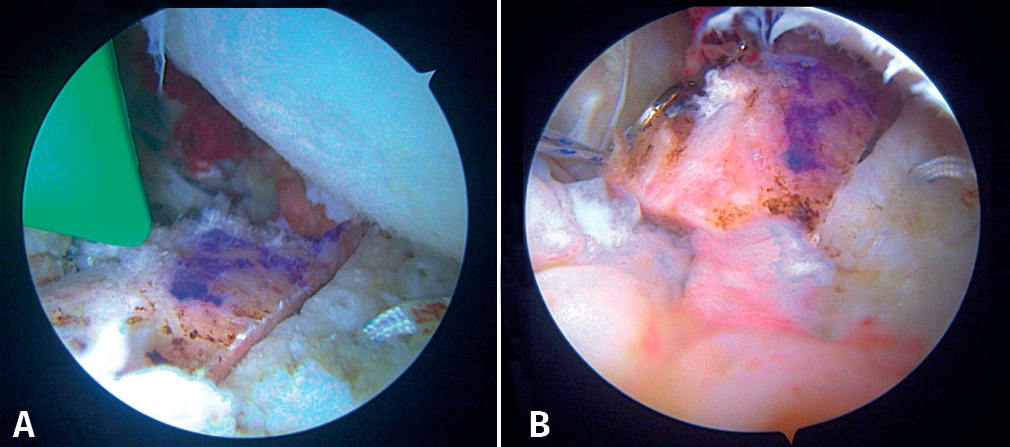

First, the glenoid is debrided with the aid of a shaver-type motor, and free bodies and bony debris are removed. The labrum and capsule are detached together from the glenoid margin, creating a wide recess to accommodate the graft, and the surface is prepared by creating bleeding edges with a burr. Then, using a posteroinferior auxiliary portal established under direct vision (Figure 3A), remplissage is started with debridement of the Hill-Sachs lesion and the placement of two bone implants - in this case HealicoilRegenesorb® (Smith & Nephew Inc., Andover, MA, USA) 4.5 mm double suture Ultrabraid® N.2 (Smith & Nephew Inc., Andover, MA, USA ) (Figures 3B and 3C). The 8 extremities are retrieved, passing them through the capsule approximately 1 cm apart and using a Sling-Shot® device (Stryker) (Figures 3D, 3E and 3F). The extremities are left untied in the posterior portal.

During this time, a second surgeon prepares the graft, giving it a rectangular shape and a size of 20 × 10 × 10 mm. To do so, he/she uses the instruments of the Glenoid Bone Loss® system (Smith & Nephew), drilling two holes with a 2.8 mm drill and spaced 10 mm apart, assisted by the specific graft preparation forceps (Figure 4A).

On the preparation table, one suture of the upper loop is passed through the upper orifice of the bone block and the lower loop through the lower orifice. These two suture loops are then used to close the double EndoButton® (Smith & Nephew) and thread the implant through each orifice of the block. Tightening is applied until both buttons are seated on the free surface of the bone block (Figure 4B).